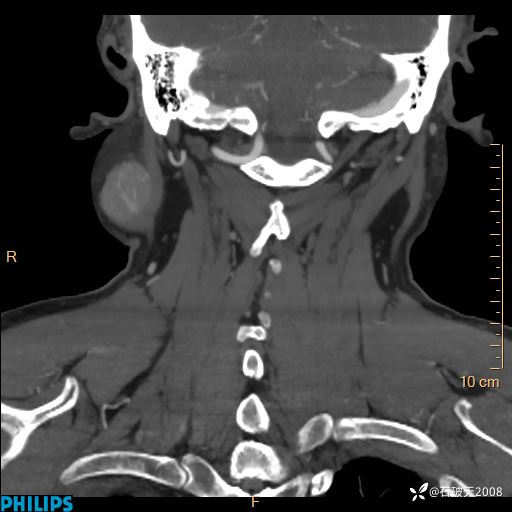

病例分享:颈部占位,一周后公布病理

男 57岁 主 诉:发现右侧颌下肿物1月余。

现病史:1月余前家属发现右侧颌下肿物。局部皮肤无红肿、热痛,无吞咽困难,无异物感,无恶心、呕吐,无头痛、头晕,无胸闷、胸痛,无发热、咳嗽、咳痰及呼吸困难。于我院行体表肿块彩超检查(2024.03.15我院)示:右侧耳下皮下软组织内低回声,未治疗。今为进一步治疗门诊以“腮腺肿瘤”为诊断收住我科,发病来患者神志清,精神可,饮食、睡眠及大小便正常,体重无明显下降。

动脉期